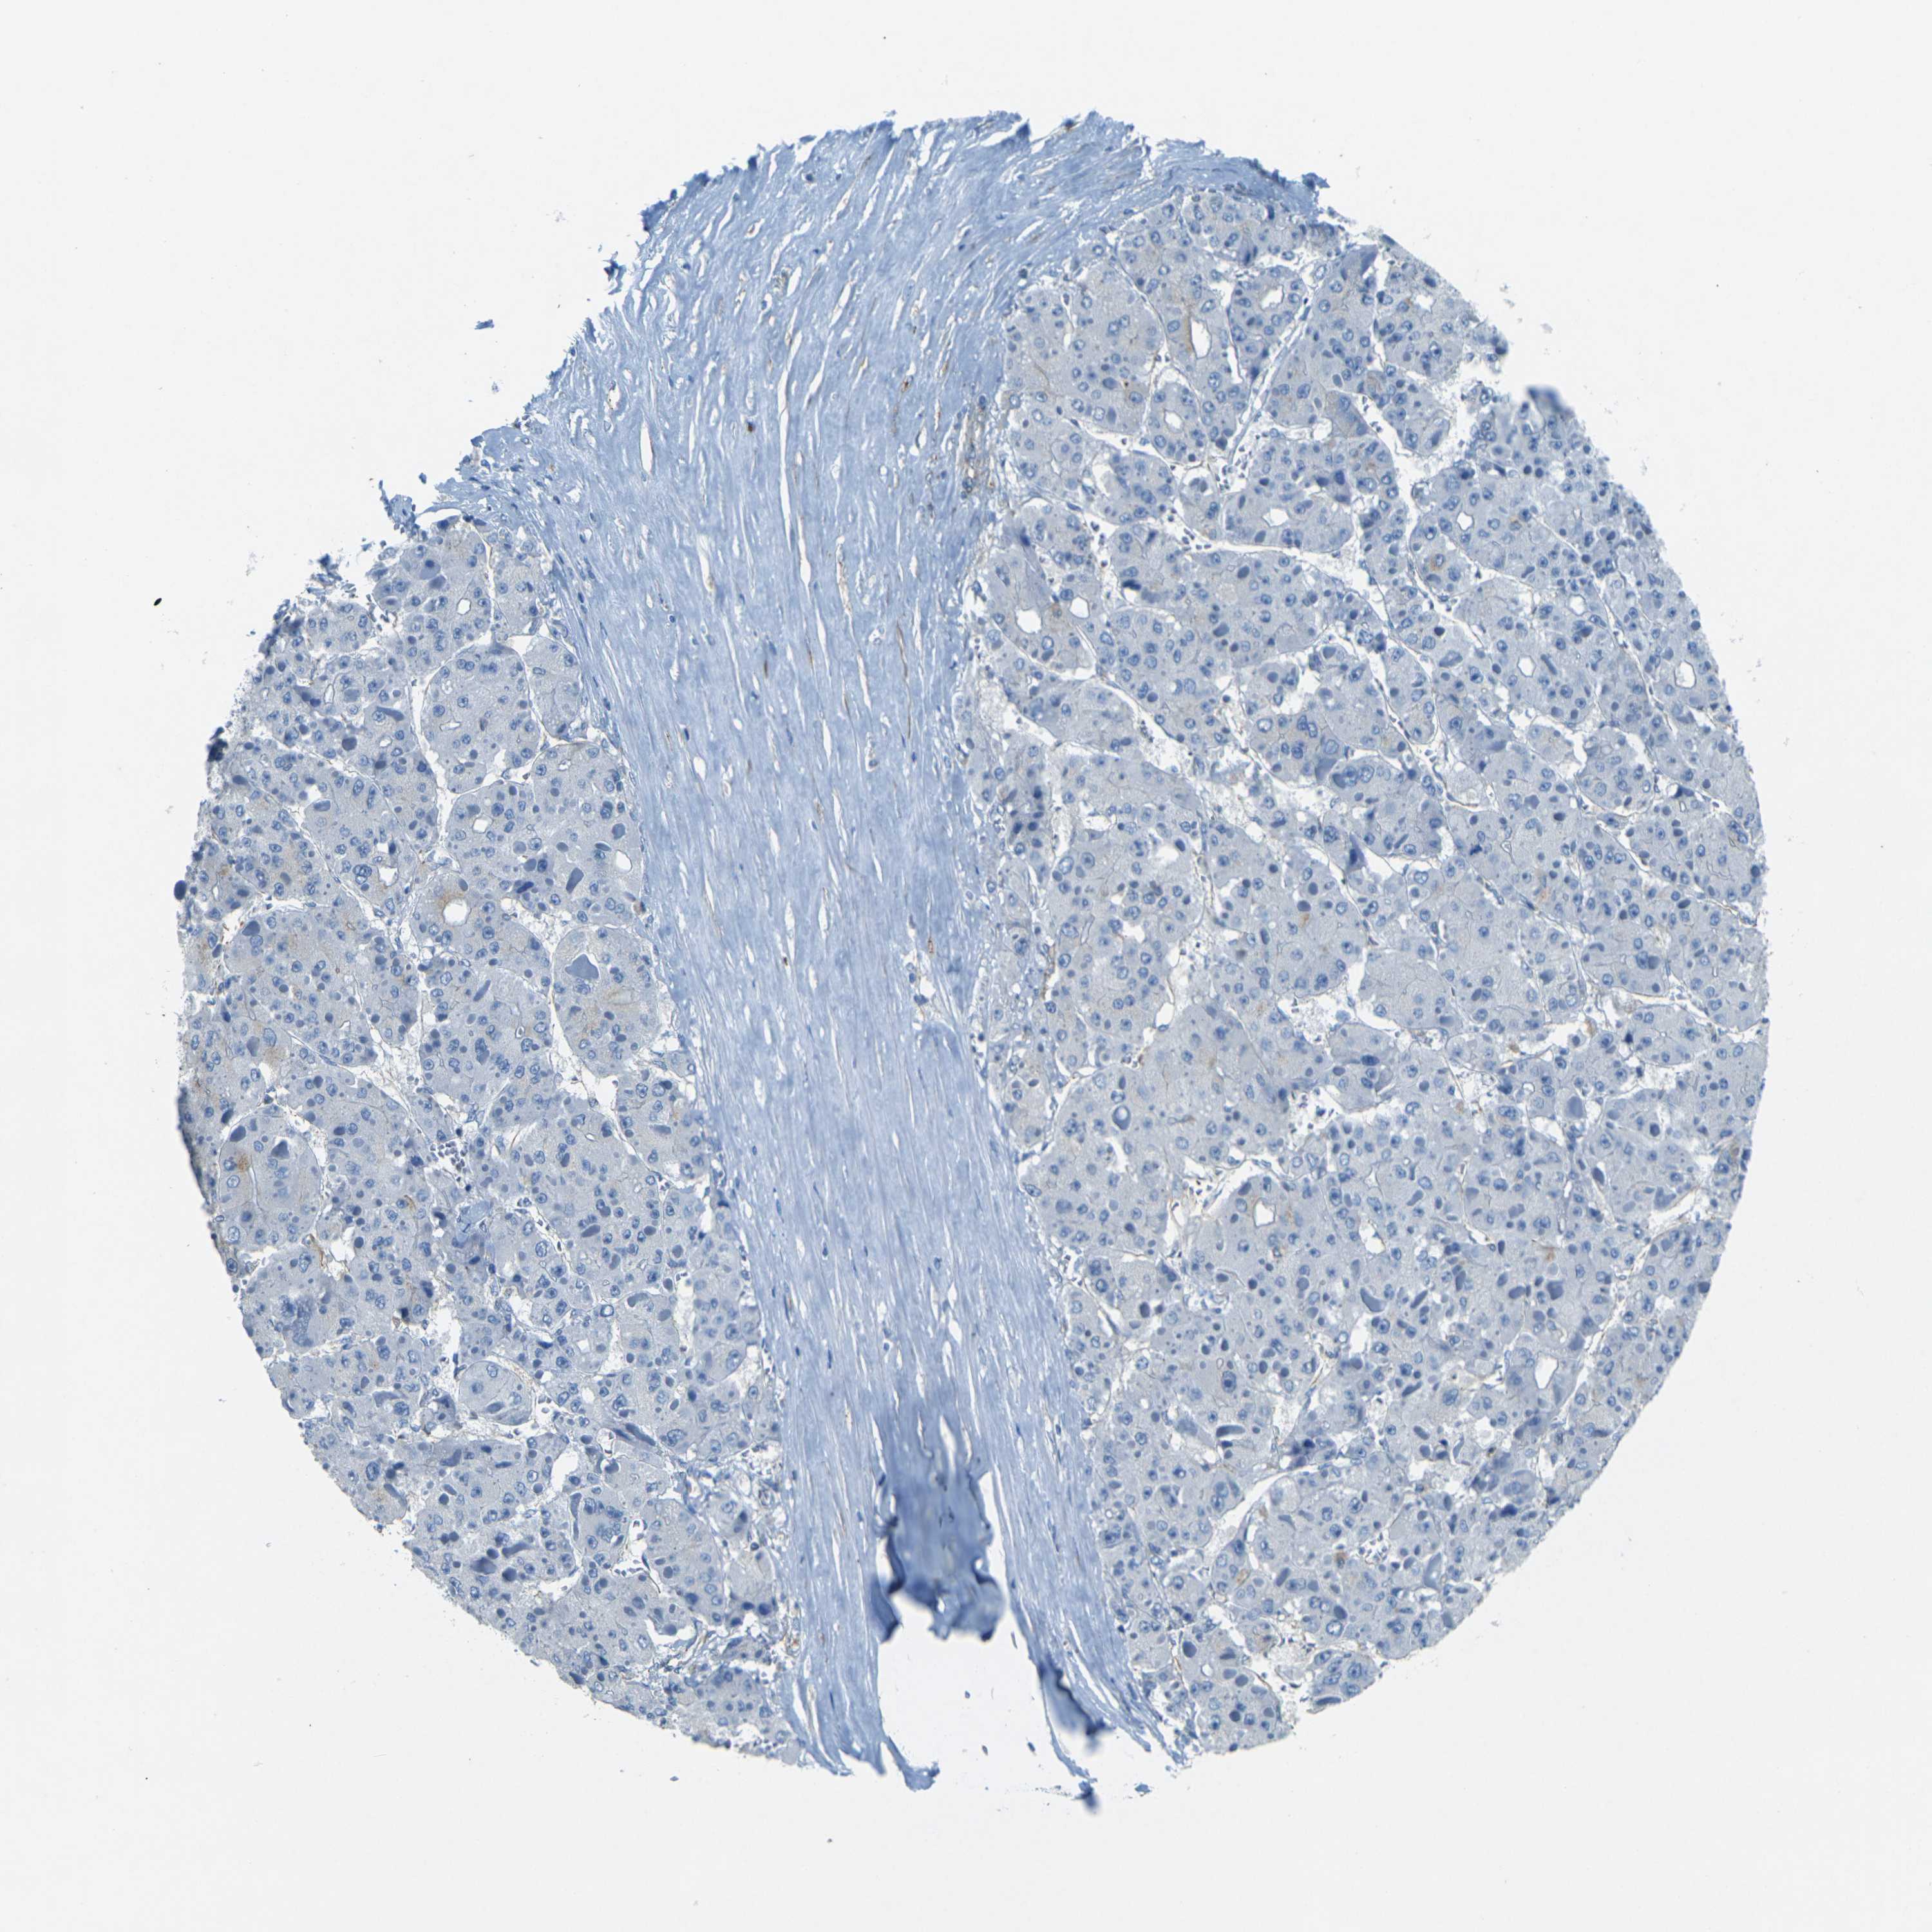

LIVER CANCER - Protein expressioni

A mouse-over function shows sample information and annotation data. Click on an image to view it in a full screen mode. Samples can be filtered based on level of antibody staining by selecting one or several of the following categories: high, medium, low and not detected. The assay and annotation is described here.

Note that samples used for immunohistochemistry by the Human Protein Atlas do not correspond to samples in the TCGA dataset.

Antibody stainingi

Antibody staining in the annotated cell types in the current human tissue is reported as not detected, low, medium, or high, based on conventional immunohistochemistry profiling in selected tissues. This score is based on the combination of the staining intensity and fraction of stained cells.

Each image is clickable and will lead to virtual microscopy that enables deeper exploration of all samples and also displays staining intensity scores, fraction scores and subcellular localization as well as patient and tissue information for each sample.

Antibody HPA006889

Antibody CAB011498

Cholangiocarcinoma

Carcinoma, Hepatocellular, NOS